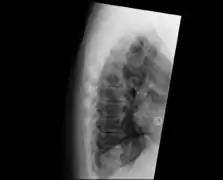

| DISH in an 80 year old female, also with T11 fracture. | |

Confluent ossification of multiple contiguous vertebral bodies in diffuse idiopathic skeletal hyperostosis (DISH)

"Melted candle wax" appearance of calcification and ossification in diffuse idiopathic skeletal hyperostosis (DISH). Note the preponderance on the patient's left side (right side of image).